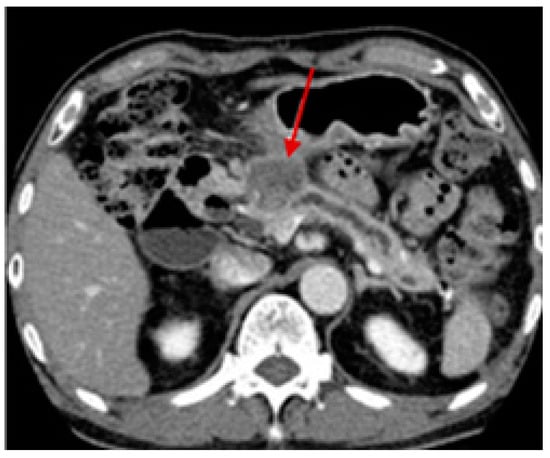

- Lee, E.S.; Lee, J.M. Imaging Diagnosis of Pancreatic Cancer: A State-of-the-Art Review. World J. Gastroenterol. 2014, 20, 7864–7877. [Google Scholar] [CrossRef] [PubMed]